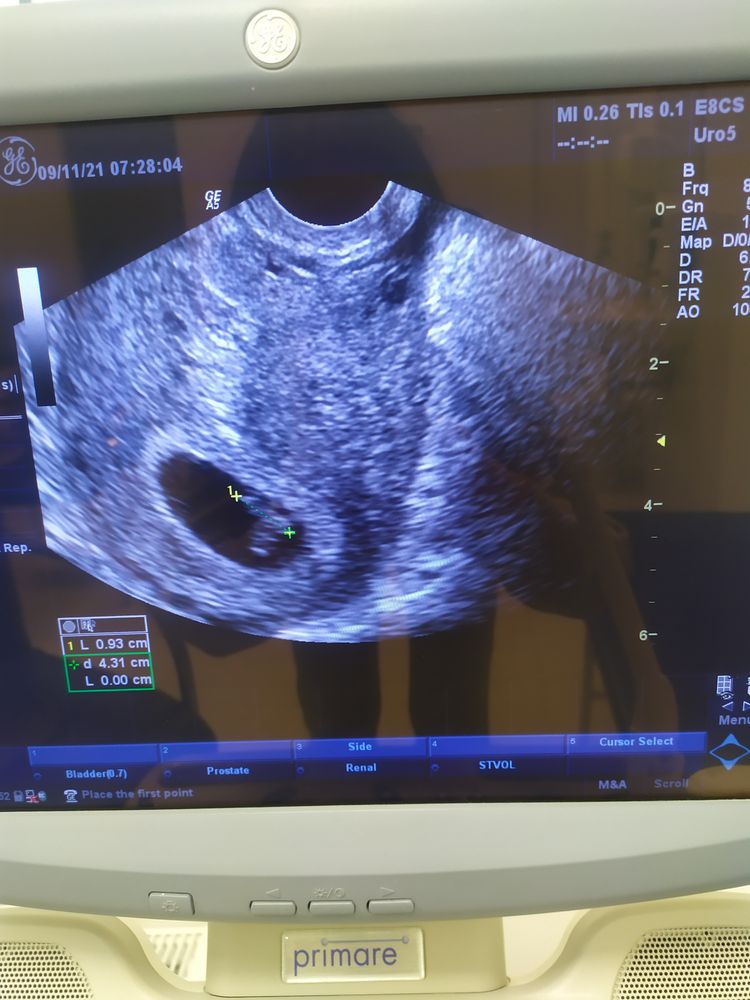

Мамуська Дианюськи и Данюськи, самый заразный чих на тебя 😘 Мы растём , токсикоз отпускает. Грудь болит страшно . На той неделе была на УЗИ. Изображение Выросла моя фасолинка